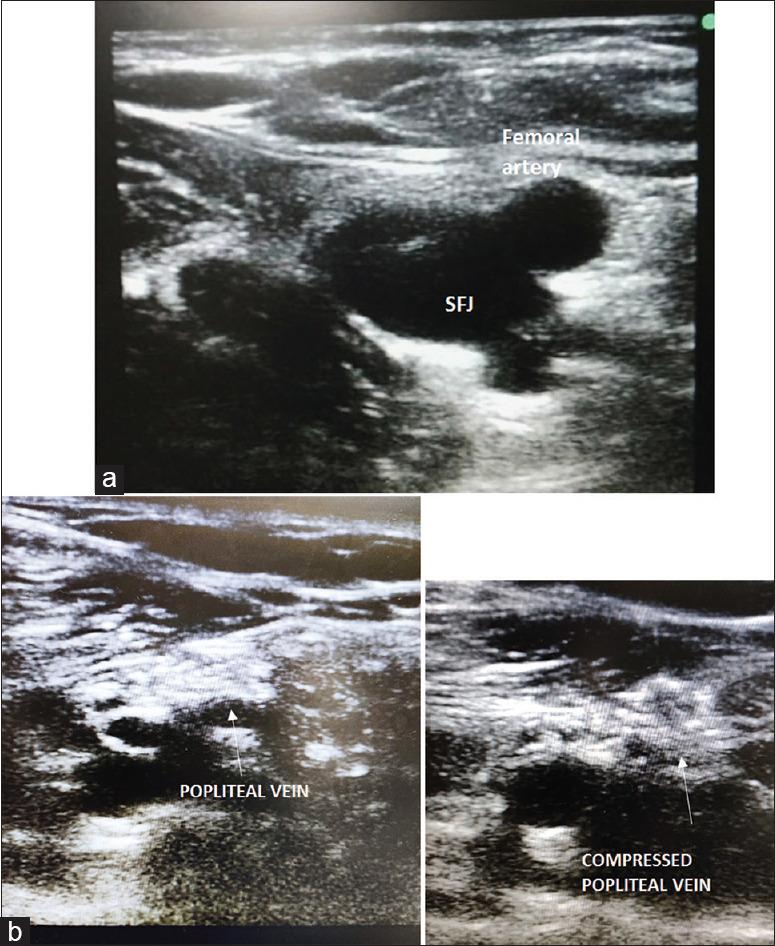

After the detection of novel coronavirus (2019) as the cause of a cluster of pneumonia in Wuhan, China, at the end of 2019, more than 10 million confirmed cases of coronavirus disease 2019 (COVID-19) have been reported around the globe. In the COVID-19 intensive care unit (ICU), the use of stethoscope is minimal for obvious reasons. Shifting of COVID-19 patients out of ICU setup increases the risk of transmission of infection to health-care workers as well as jeopardizes the safety of patients. Hence, diagnostic imaging has emerged as a fundamental component of the current management of COVID-19. Lung ultrasound (LUS) imaging has become a safe bedside imaging alternative that does not expose the patient to radiation and minimizes the risk of contamination. Ultrasound (USG) can be used to scan almost all vital organs (heart, kidney, vascular, brain, etc.) and also help in rapid decision-making regarding the management of COVID-19 patients. In this note, we review the current state of the art of LUS in evaluating pulmonary changes induced by COVID-19. The goal is to identify characteristic sonographic findings most suited for the diagnosis of COVID-19 pneumonia infections as well as to assess the impact of infection on other organs and utilizing the same in the management of COVID patients without compromising on the safety of patient or health-care provider.

2019年末在中国武汉发现新型冠状病毒(2019)是一组肺炎病例的病因后,全球已报告超过1000万例2019冠状病毒病(COVID-19)确诊病例。在COVID-19重症监护病房(ICU),由于显而易见的原因,听诊器的使用极少。将COVID-19患者转出ICU会增加感染传播给医护人员的风险,同时也危及患者安全。因此,诊断成像已成为当前COVID-19管理的一个基本组成部分。肺部超声(LUS)成像已成为一种安全的床旁成像选择,不会使患者暴露于辐射下,并将污染风险降至最低。超声(USG)可用于扫描几乎所有重要器官(心脏、肾脏、血管、大脑等),也有助于对COVID-19患者的管理做出快速决策。在本笔记中,我们回顾了LUS在评估COVID-19引起的肺部变化方面的当前技术水平。目标是确定最适合诊断COVID-19肺炎感染的特征性超声表现,以及评估感染对其他器官的影响,并在不损害患者或医护人员安全的情况下将其用于COVID患者的管理。